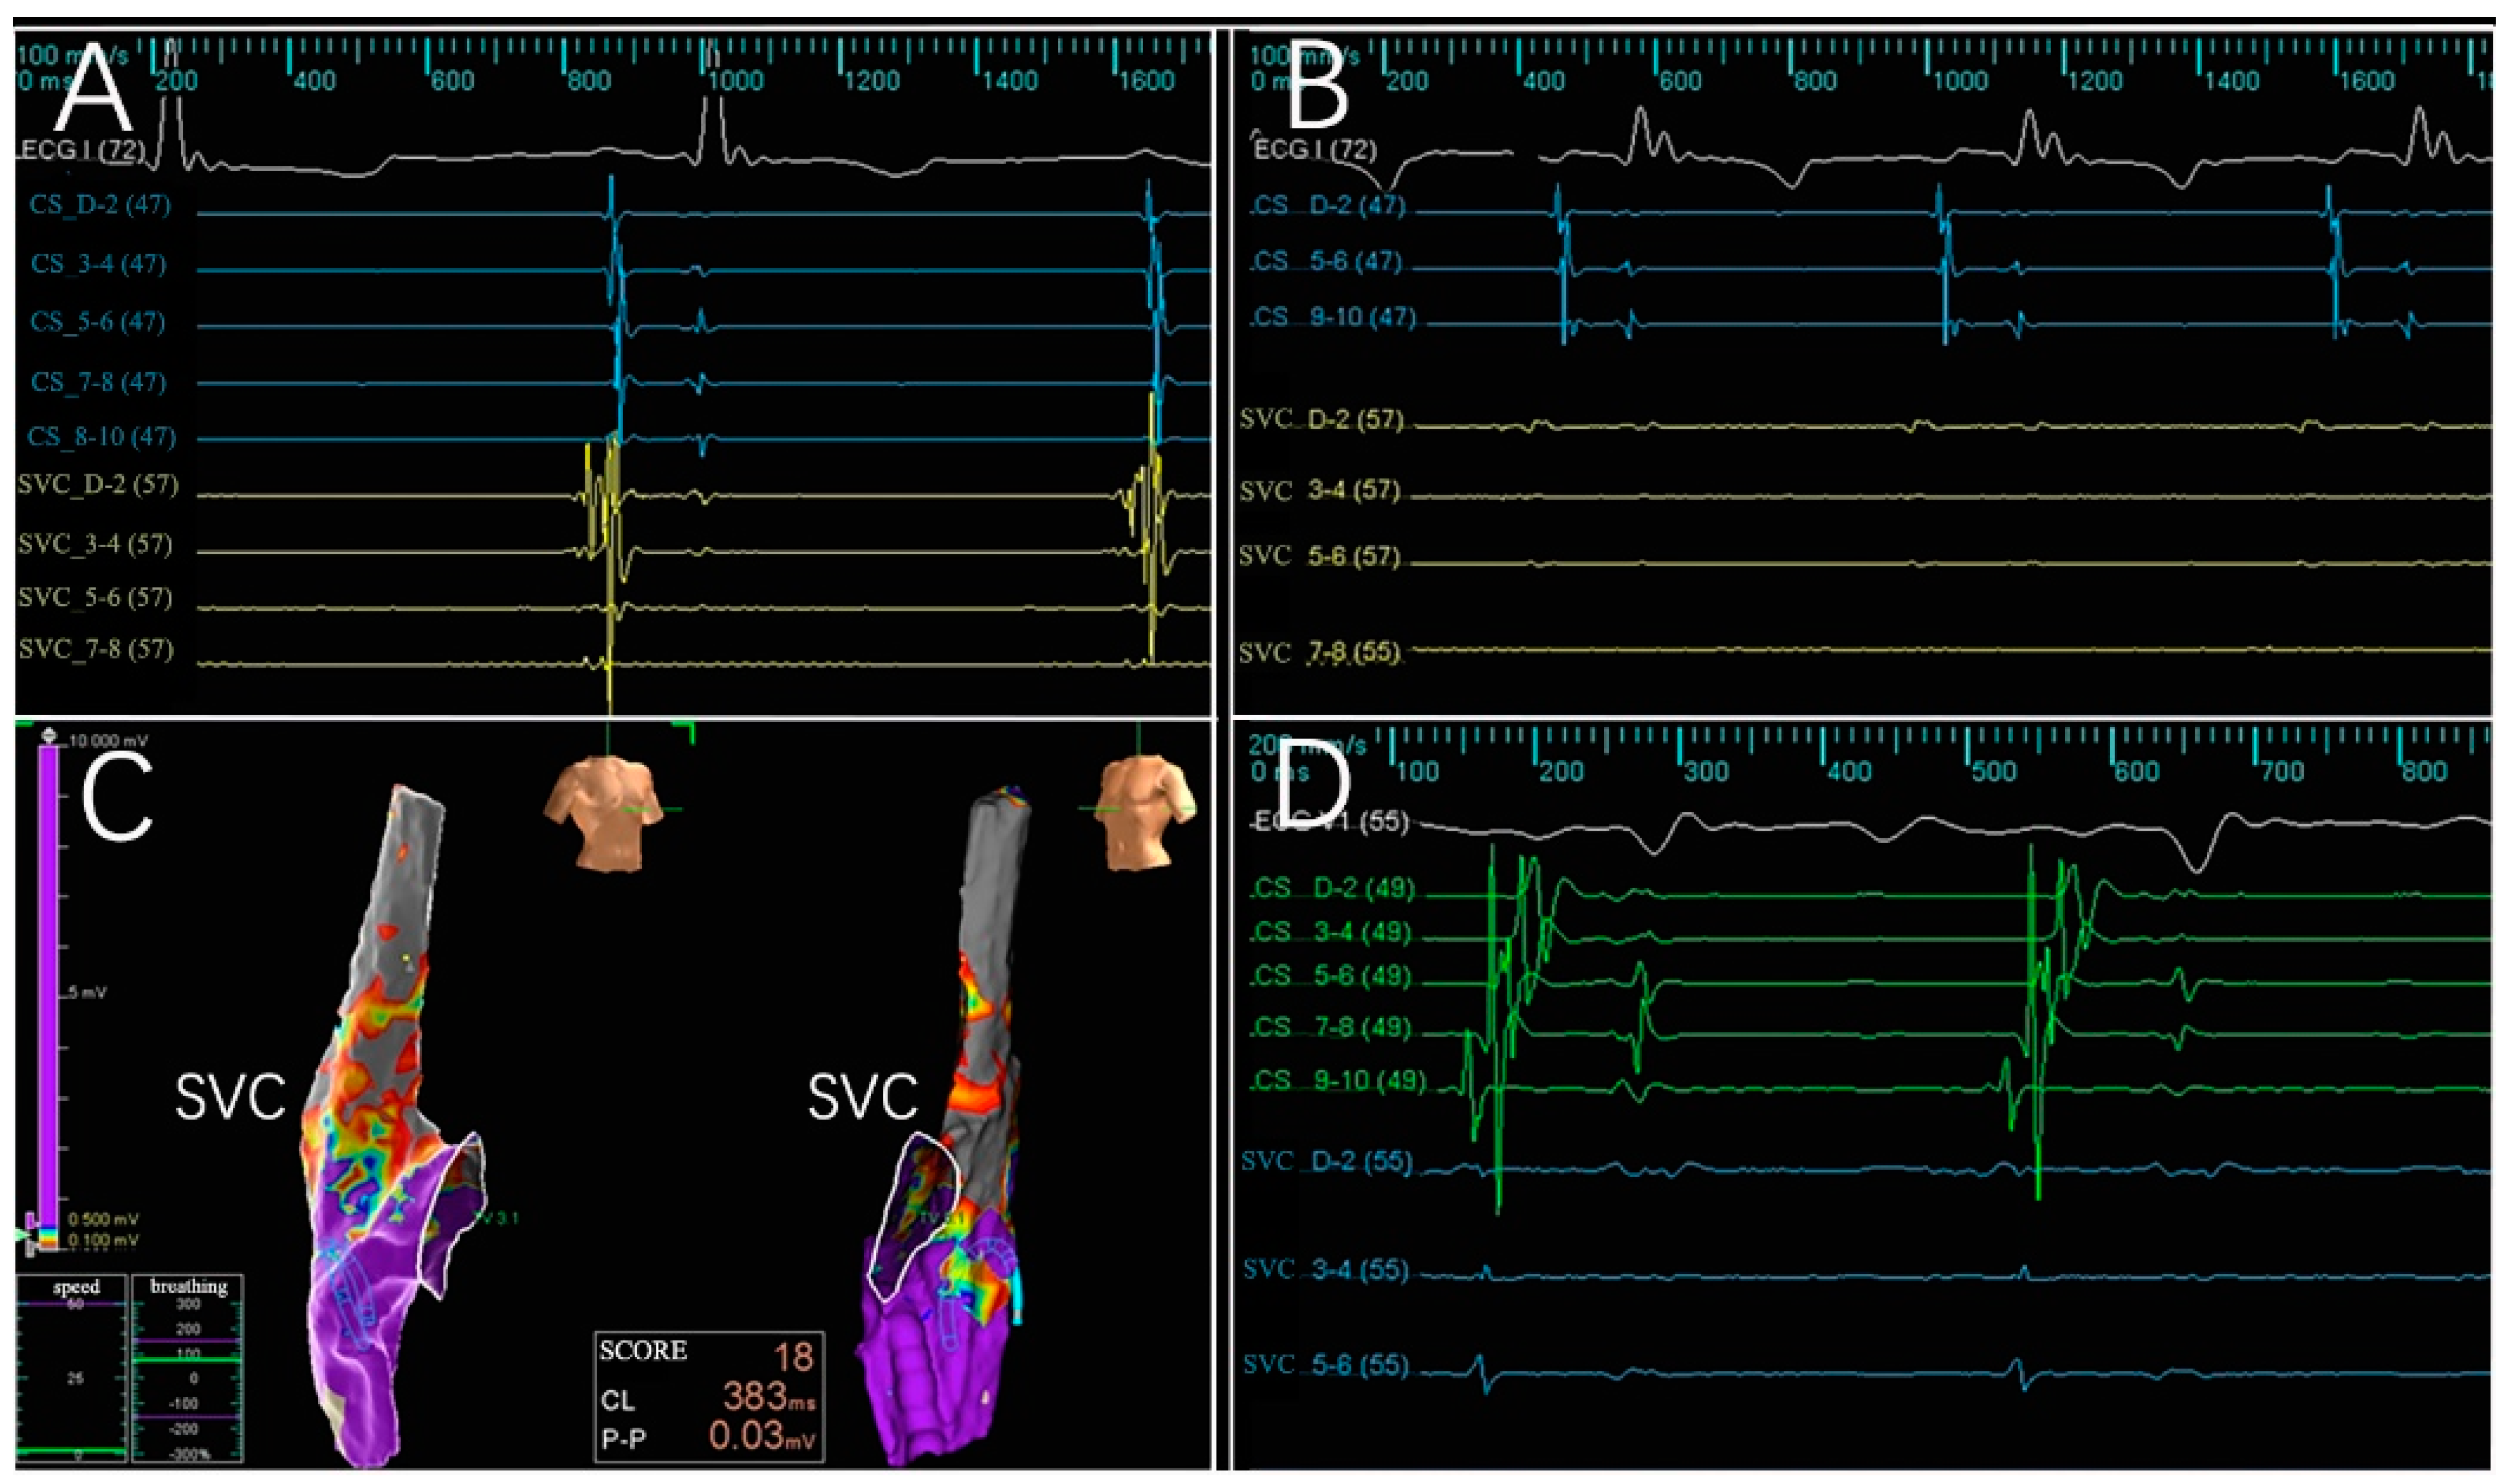

3.2. Electrogram, Voltage Mapping, and Complications